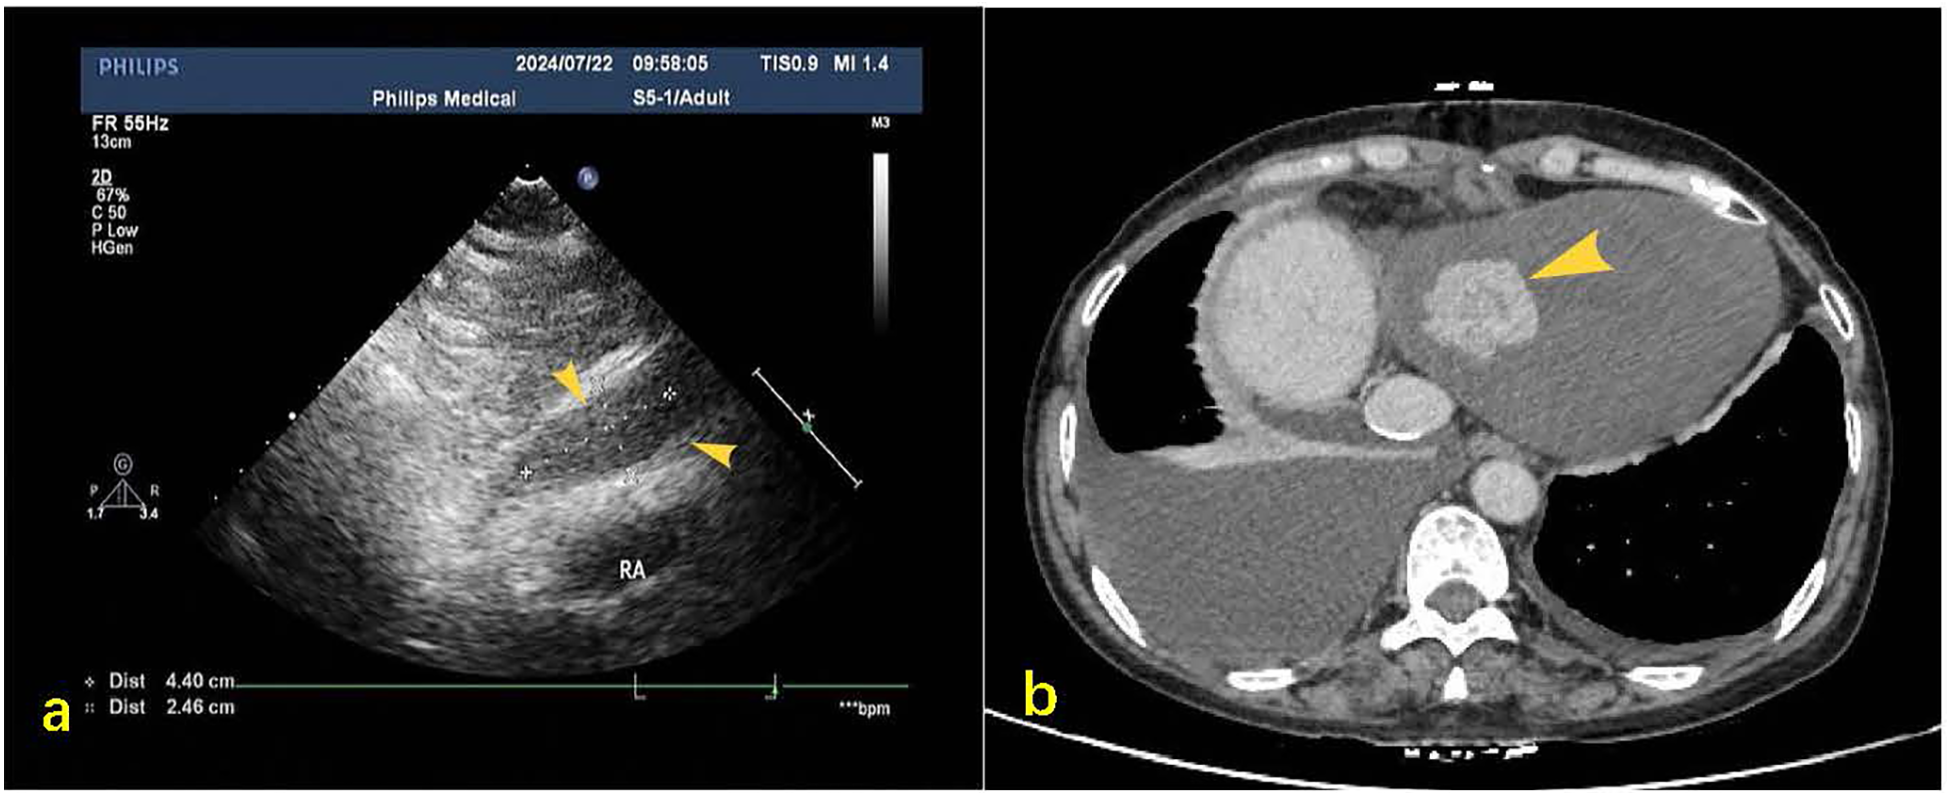

A 55-year-old female patient with a 2-week history of bilateral lower extremity edema was admitted to our department (July 4, 2024), who had a history of left liver lobectomy for intrahepatic bile duct stones. Laboratory tests on admission showed that the alpha-fetoprotein (AFP) value was 225 times higher than the upper limit of the normal reference range (0–15 ug/L), and the carbohydrate antigen (CA125) value was 9 times higher than the upper limit of the normal reference range (0–20 U/mL). Large amounts of pericardial effusion were seen on cardiac ultrasonography. Following the evacuation of the effusion, a faint echogenic mass of approximately 4.4 × 2.5 cm was observed in the pericardial cavity near the bottom of the right heart. (Figure 1a, July 22, 2024). And, an enhanced computed tomography (CT) revealed an intrapericardial mass measuring around 4.0 × 2.1 cm and a right pleural effusion, but no liver mass was detected (Figure 1b, July 6, 2024). Subsequently, the systemic positron emission tomography (PET) examination showed an abnormal uptake of 18-fluoro-2-deoxyglucose in the areas of the upper margin of the hepatic caudate lobe, the right margin of the heart and the banded soft tissue beside the ascending aorta (Figure 2, July 11, 2024). Utilizing hepatobiliary specific magnetic resonance contrast agents in enhanced magnetic resonance imaging (MRI), we discovered a circular enhancement in the left hepatic lobe close to the diaphragm surface with a diameter of 0.6 cm (Figure 3, July 14, 2024). Piercing fluids from both pericardial and thoracic cavities were bloody exudate, and no malignant cells were detected. On July 24th, 2024, surgical exploration was performed and an irregular and sessile fish-fleshed-like soft tissue mass in the pericardium near the bottom of the heart was found, measuring approximately 4 cm × 5 cm. Meanwhile, a tissue with a size of about 8 cm*7.2 cm*1.6 cm was removed during the operation, and a cardiac malignant tumor was identified by pathological biopsy. The immunohistochemistry results indicated a metastatic hepatic adenocarcinoma or metastasis of hepatocellular carcinoma (Figure 4). During surgical exploration the mass was found not to invade the myocardium but demonstrated ill-defined margins with the diaphragm. Subsequent diaphragmatic incision revealed an intact hepatic surface, suggesting low probability of direct hepatocellular carcinoma extension to the heart. Intraoperative identification of multiple soft tissue masses in the pericardial transverse and oblique sinuses prompted cytoreductive surgery for widespread metastases. Postoperative therapy with Lenvatinib combined with camrelizumab was initiated. During monthly outpatient follow-ups, serially elevated AFP levels reaching 7,920 times the upper reference limit were observed (Supplementary Data Figure S1). Surveillance CT demonstrated progressive massive pleural effusion with newly developed thoracic and abdominal cavity metastases. The patient received palliative care and died on January 3, 2025.

Figure 1

(a) Post-pericardiocentesis echocardiographic follow-up revealed a hypoechoic mass measuring approximately 44 × 25 mm in the pericardial cavity at the base of the right heart during subxiphoid examination (yellow arrow). (b) Contrast-enhanced CT on mediastinal window settings reveals an irregular soft tissue mass located at the base of the heart and the inferior aspect of the right atrium, measuring approximately 4.0 × 2.1 cm (indicated by the yellow arrow), exhibiting heterogeneous enhancement.